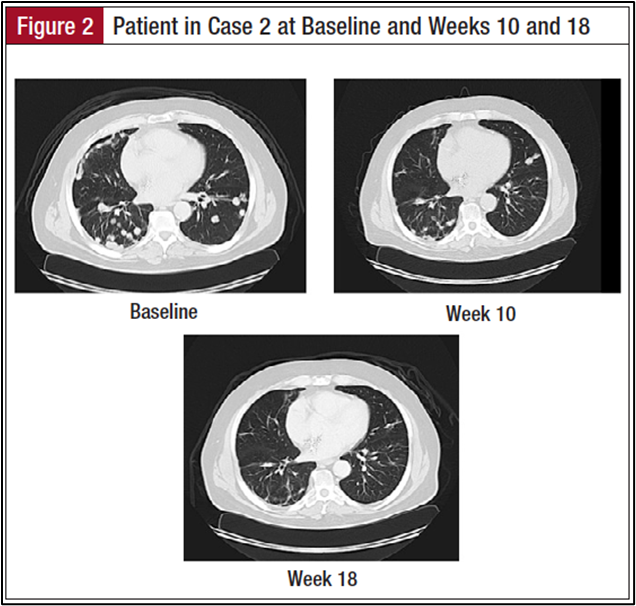

The patient is a 60-year-old man with a 5–pack-year smoking history who quit smoking 31 years prior to presentation (Figure 1). He began complaining of right arm pain in November 2011. A chest computed tomography (CT) scan showed a 4.5-cm lesion in the right upper lobe abutting the pleura. A percutaneous needle biopsy of the lung mass was undertaken, which showed sheets of malignant-appearing cells with glandular features and areas of necrosis. The tumor cells were positive for TTF1, napsin A, cytokeratin (CK) 7, and CD56, and negative for CK20, CK5/6, p63, chromogranin, and synaptophysin consistent with primary adenocarcinoma of the lung. Upon review of his case in a multidisciplinary setting, he was offered chemotherapy with cisplatin and pemetrexed as an initial course of therapy. He had an evaluable response to chemotherapy with evidence of tumor shrinkage, enabling him to be referred for a surgical resection. He underwent a right upper lobectomy. Pathology was consistent with high-grade carcinoma with a prominent neuroendocrine pattern. The tumor was 4.0 cm in greatest dimension and approached the perivascular soft tissue. Mediastinal lymph nodes were negative for any evidence of malignancy. He did not receive chemotherapy in the adjuvant setting.

Six months following the patient’s surgery, surveillance CT scans showed evidence of new lesions in the left lung. Percutaneous biopsy of one of the pulmonary lesions was consistent with recurrent TTF1-positive, CK 7-positive, napsin A-negative, and thyroglobulin-negative cells consistent with adenocarcinoma of the lung. He was negative for EGFR and ALK mutations. Because of his prior experience with chemotherapy, the patient was reluctant to undergo further chemotherapy for his now stage IV disease. He opted to participate in a dendritic cell vaccine study to which he initially had a mixed response followed by progression 3 months after enrollment. Upon progression, he was offered treatment with systemic chemotherapy. However, the patient requested to pursue various trial options, ultimately presenting to our clinic for consideration of an immunotherapy trial with a checkpoint inhibitor.

In July 2013, the patient was evaluated for an anti–PD-1 antibody immunotherapy trial and underwent a biopsy of a pulmonary lesion, which was tested for PD-L1 protein expression. The disease was found to express PD-L1. His CT scans prior to enrollment indicated the presence of multiple bilateral pulmonary nodules, the largest of which was 2.5 cm. There was no evidence of pleural effusion, but the patient had a small pericardial effusion. His first scan 9 weeks after initiating therapy indicated stable disease; all subsequent scans have indicated significant tumor shrinkage. The patient has tolerated therapy well with no significant side effects, except for complaint of bilateral buccal mucosal swelling and sensitivity. He has also developed oral ulcers that have been managed well with oral lidocaine and a steroid solution. He has had no other side effects, and continues to do well on the trial 1 year after enrollment.